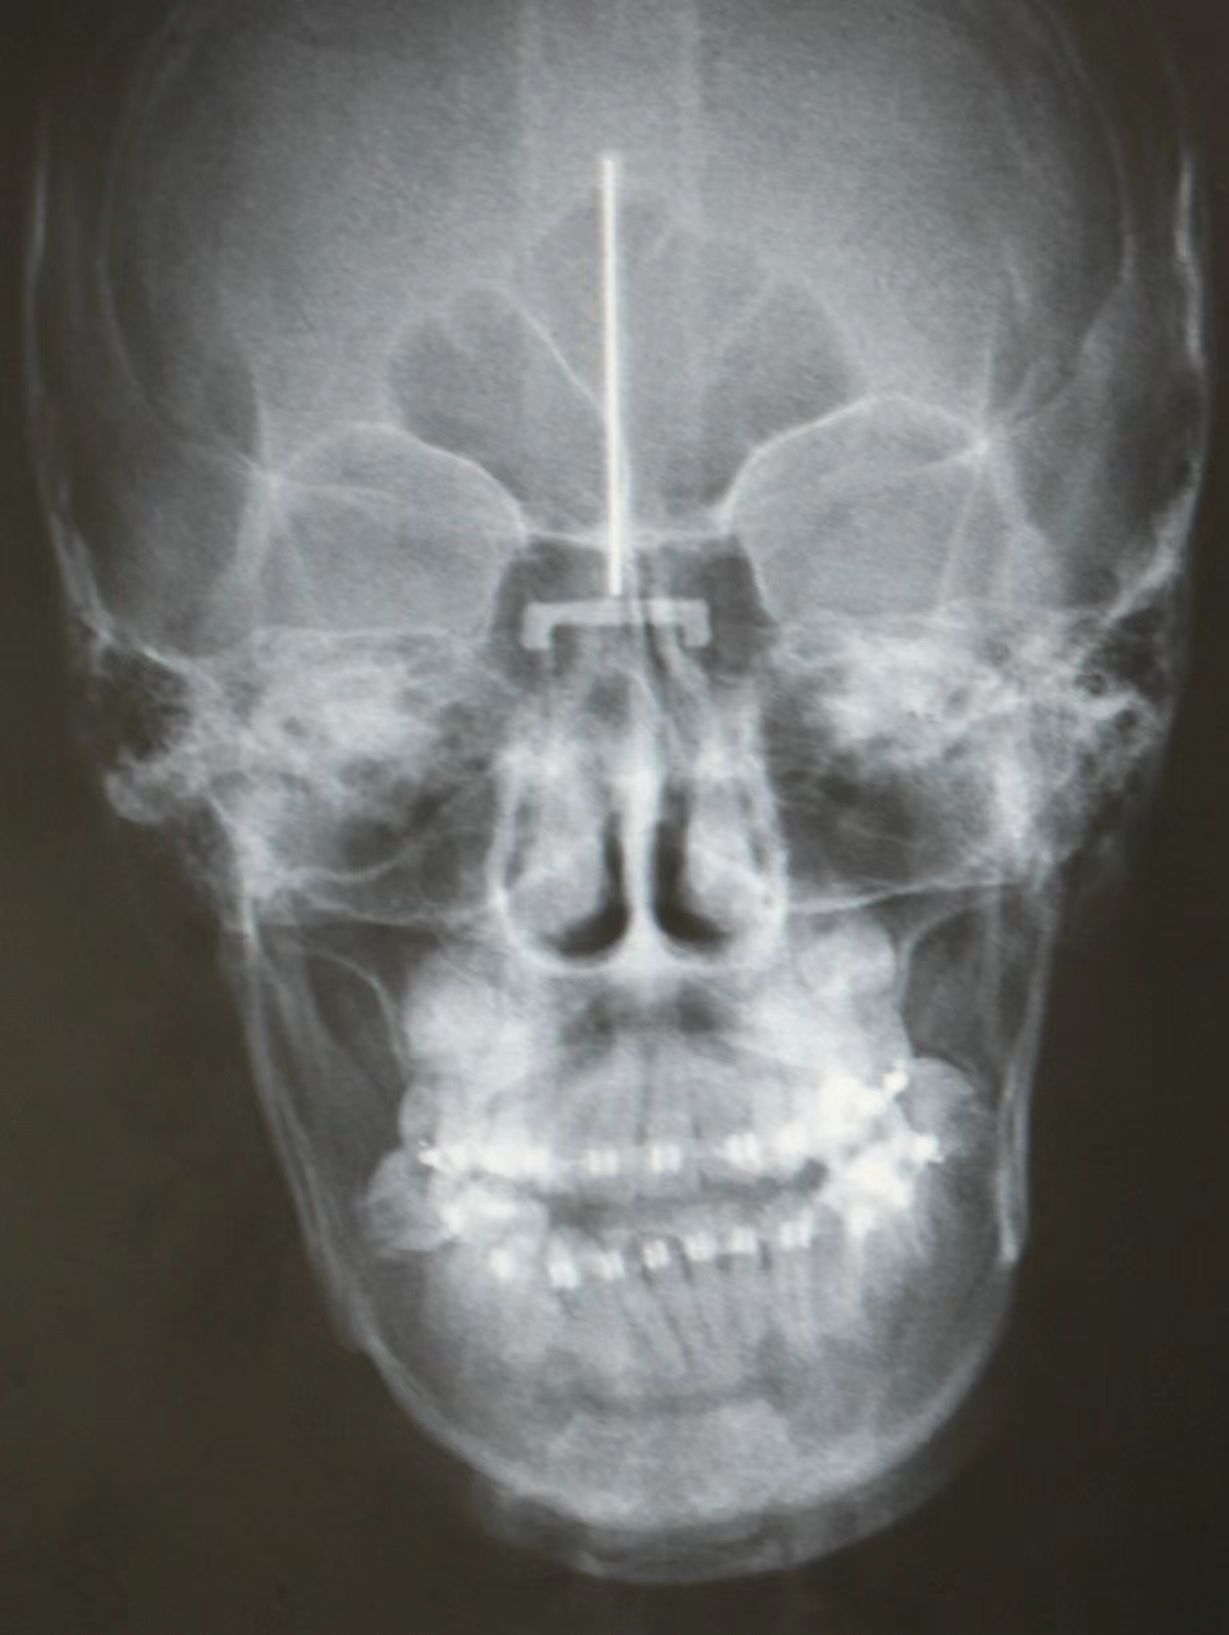

情况:不接受外科手术,在当地做了1年半的矫治,遇到困难无法进行。由外地正畸同行推荐来上海寻求非手术矫治的二手病例。武广增老师接收时的错合畸形情况,呈现严重的骨性反合偏合及侧方开合(图1-图10)。由于推荐其去口腔医院接受正颌外科手术遭到拒绝,武广增老师通过专业的检查、分析,制定一套详细的治疗计划,采用了磨牙推进器技术、武式辅弓技术等特色正畸手段获得明显效果(图2-1~图2-9)。治疗结束后也拍摄了相关照片(图3-1~图3-9)。

矫治前

图3